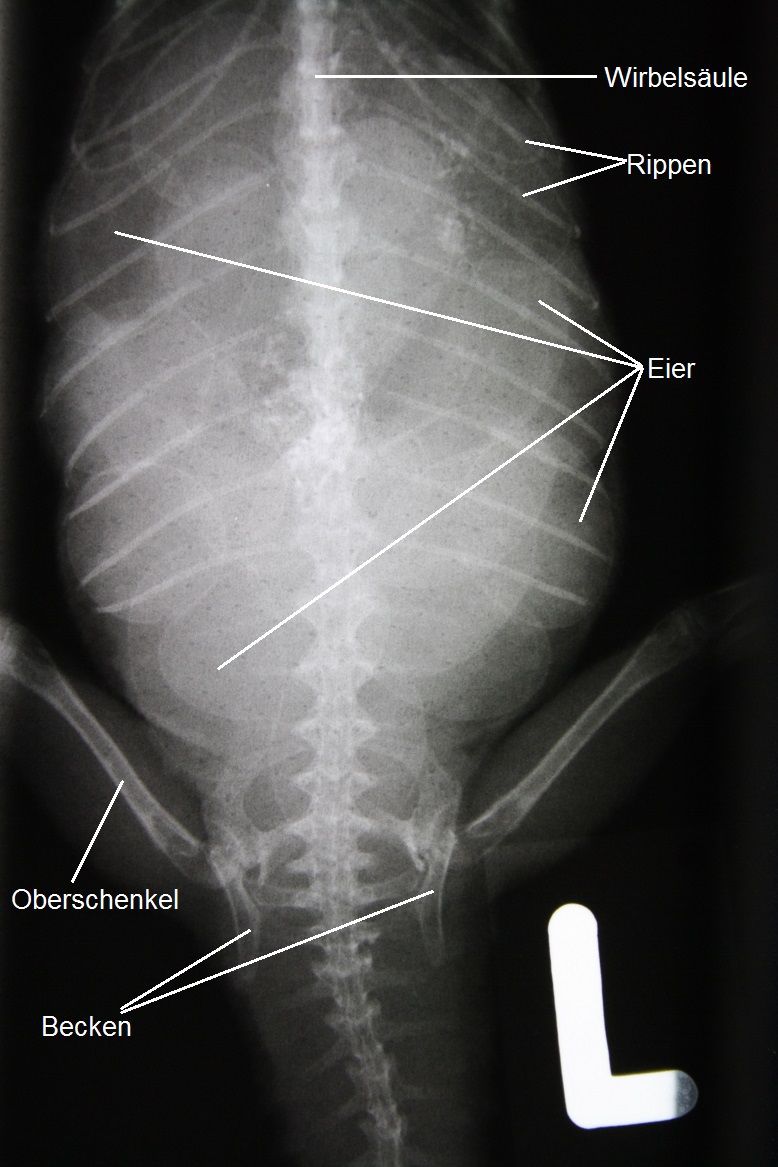

Der Bauch der Agamen-Dame kann problemlos untersucht werden; er erscheint etwas erweitert, und es lassen sich eine grössere Zahl gut erdnussgrosser Eier ertasten. Ein Röntgenbild bestätigt, dass sich rund ein Dutzend Eier im Legedarm des Tieres befinden.

Durch das veränderte Verhalten des Tieres kann davon ausgegangen werden, dass das beobachtete Bild nicht mehr als physiologisch und normal betrachtet werden kann, sondern dass es sich um eine Legenot (Eiverhalten) handelt. Hierbei gelingt es dem Tier nicht, die produzierten Eier abzulegen, was zu verschiedenen Problemen führen kann.